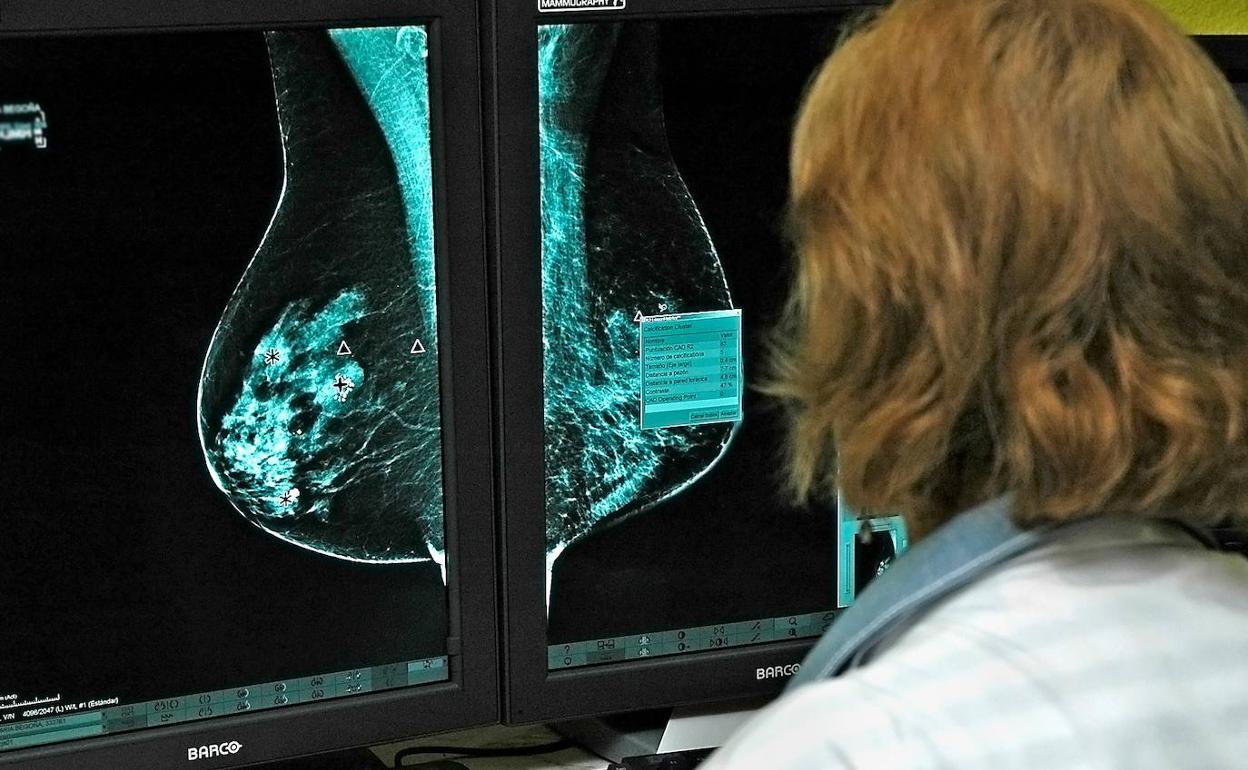

Investigadores del Laboratorio de Oncología Matemática de la Universidad de Castilla-La Mancha (UCLM) han conseguido identificar un nuevo biomarcador de imagen para pronosticar la evolución de los cánceres de mama y de pulmón a partir del desarrollo de modelos matemáticos.

El estudio ha analizado los datos de 230 pacientes oncológicos de pulmón y mama de los hospitales de Albacete y Ciudad Real con el objetivo de captar la heterogeneidad de las células tumorales. Según el profesor del Departamento de Matemáticas de la UCLM e investigador de este laboratorio, Gabriel Fernández Calvo, «a partir de imágenes médicas, los investigadores han estudiado los niveles de actividad metabólica en pacientes con tumores de pulmón y mama, o lo que es lo mismo, cómo se va reorganizando dicha actividad conforme esos tumores evolucionan».

De esta forma, el nuevo biomarcador cuantifica cómo es la evolución en tumores sólidos basándose en calcular la distancia desde el centro de masas del tumor hasta el punto de máxima actividad metabólica. El trabajo ha sido publicado en la revista científica 'Proceedings of the National Academy of Sciences of the United States of America'.